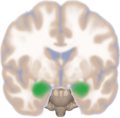

Frontal view of the amygdalae in an average human brain

Amygdala highlighted in green on coronal T1 MRI images

Amygdala highlighted in green on transversal T1 MRI images